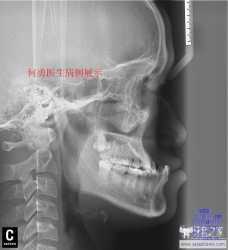

直面型

我们正畸医生追求的理想面型。建议牙套们将Gonzales-Ulloa零子午线和Ricketts审美平面区结合起来判断你是否是直面型。下面用病例展示的方式告诉牙套如何才是直面型。